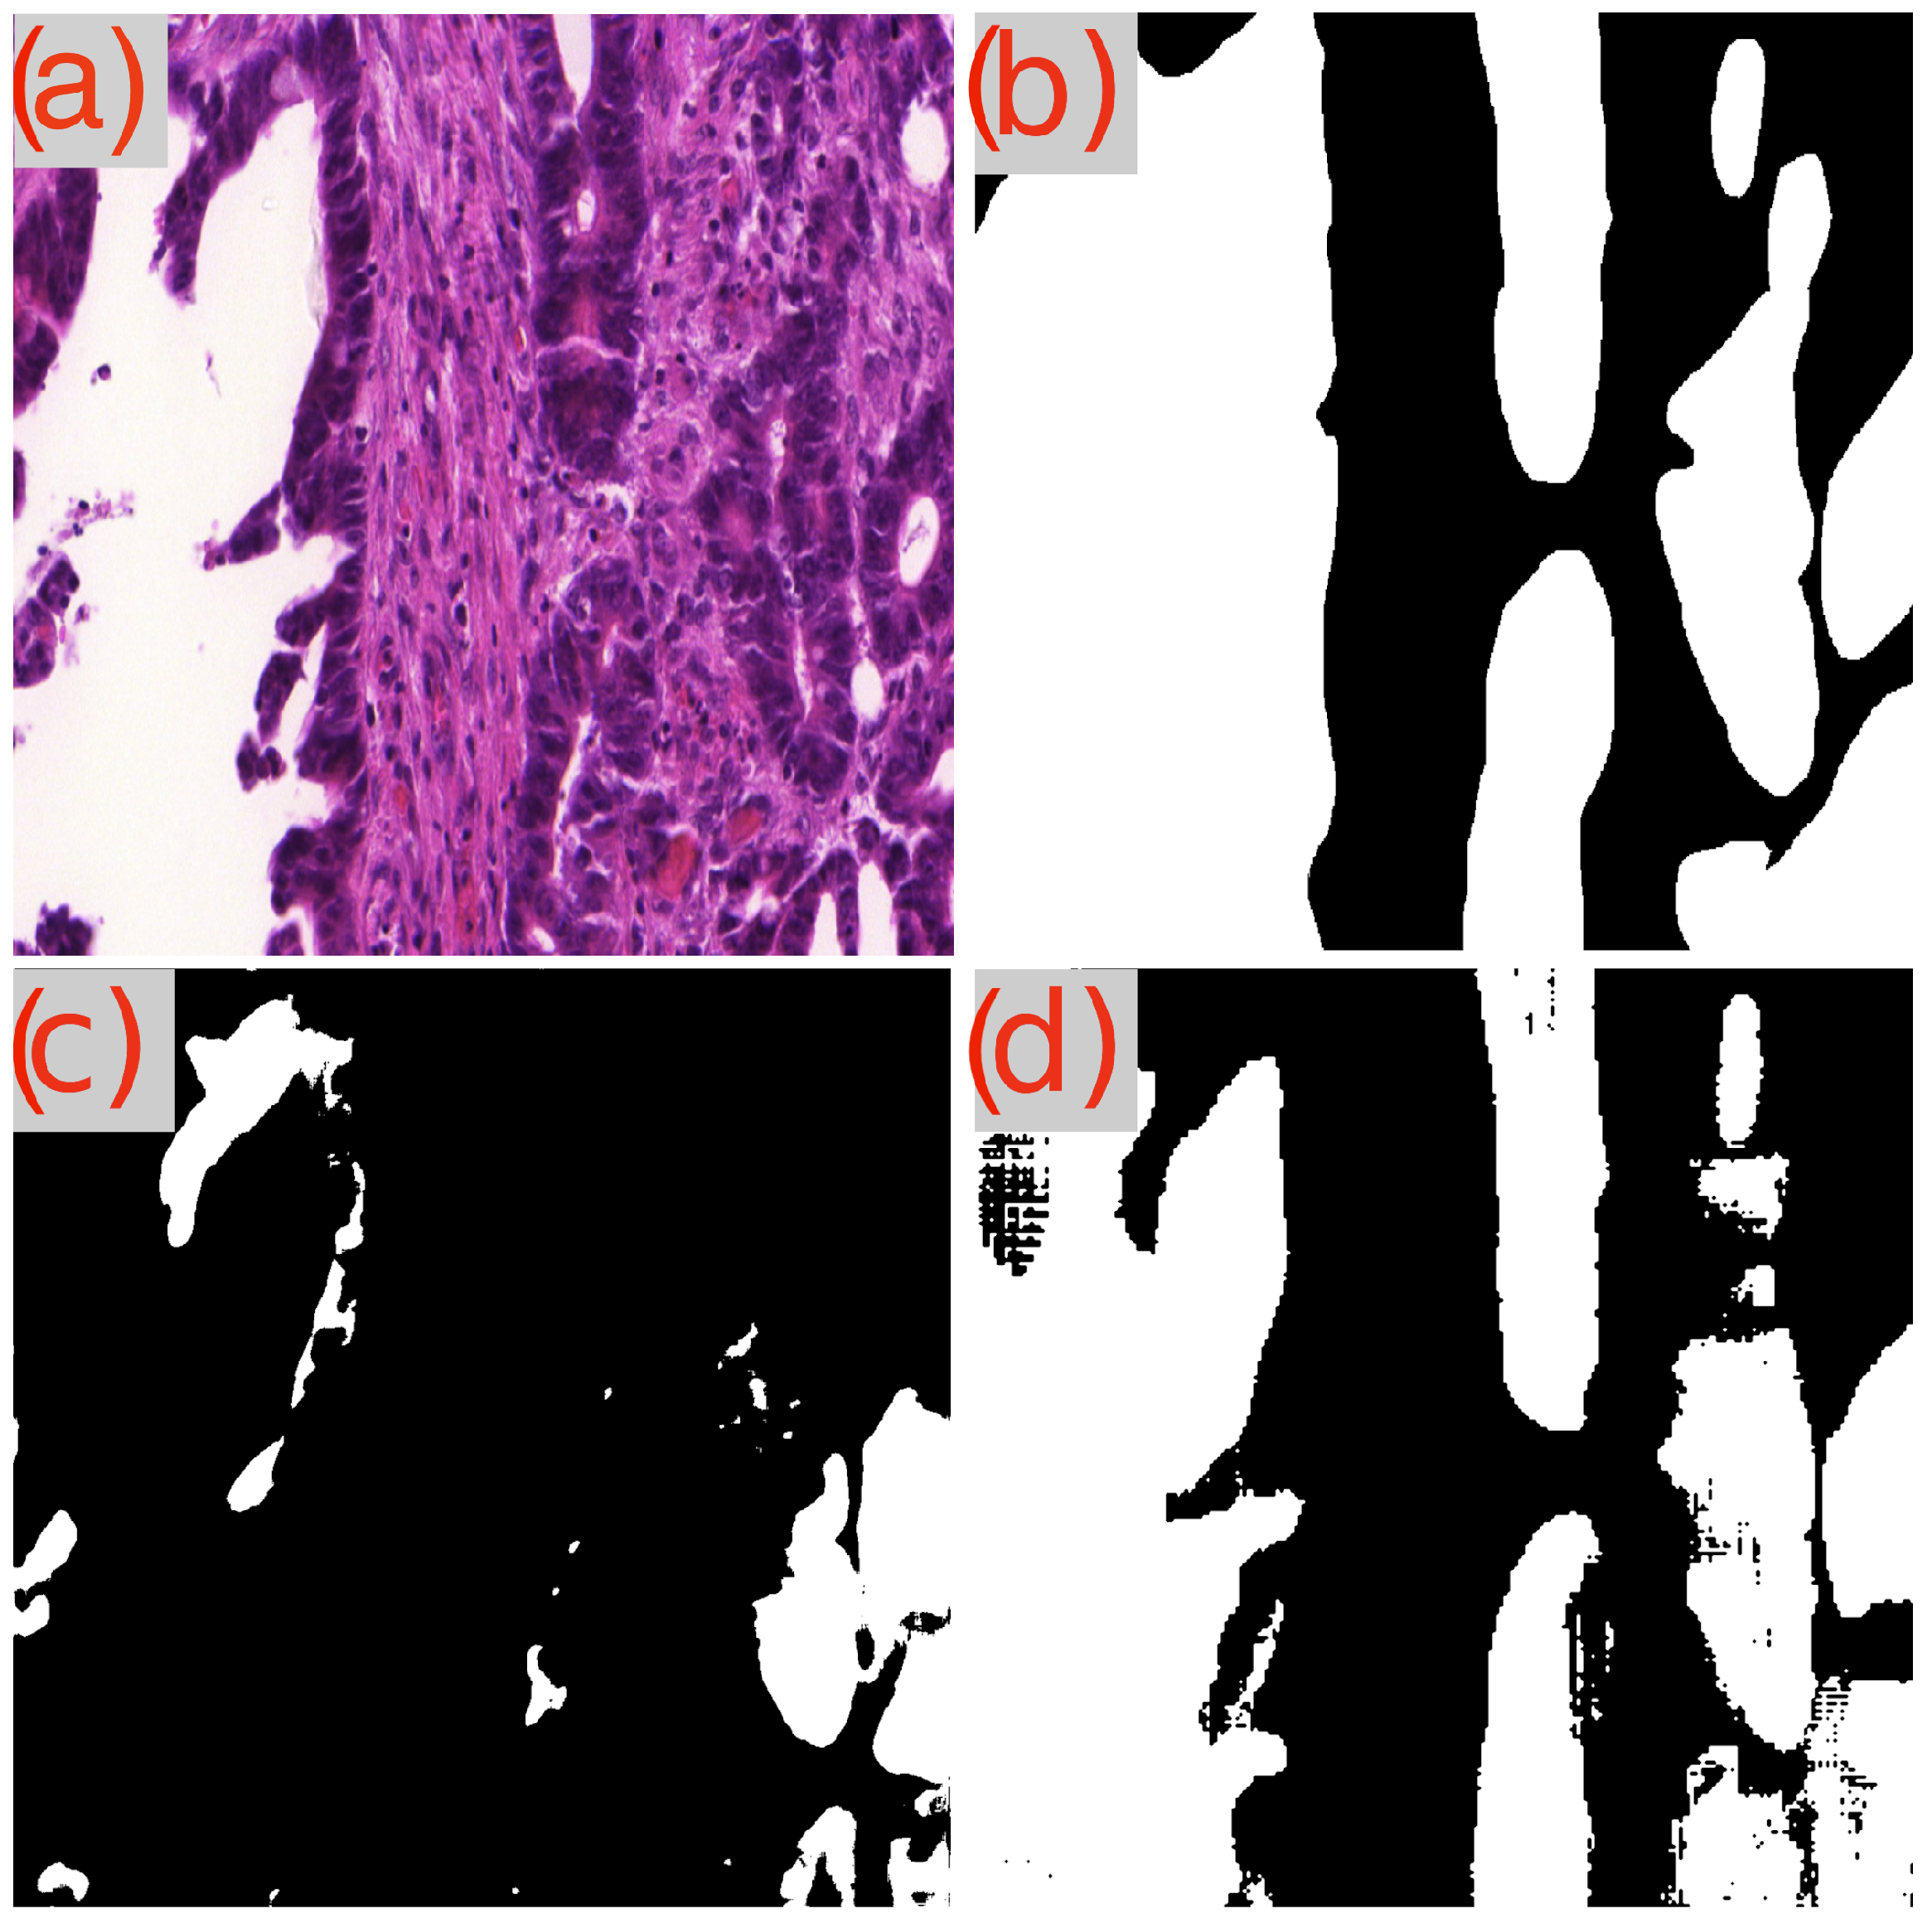

A recurring observation in Table 3 is the challenge presented by the image test_23 to the GB-SAM model, which faces difficulties across all metrics (Dice, IoU, mAP) and dataset sizes. As demonstrated in Figure 3d, GB-SAM’s segmentation is noticeably noisy, showing a tendency toward higher false positives and reduced accuracy, as evidenced by its over-segmentation and unnecessary noise alongside actual features.

Figure 3.

Segmentation results using GB-SAM and U-Net for image test_23 of the CRAG dataset: (a) H&E patch image, (b) ground truth mask, (c) U-Net predicted mask, (d) GB-SAM predicted mask.

In contrast, U-Net’s segmentation more closely matches the ground truth but lacks finer details, missing smaller features and resulting in smoother edges. This indicates U-Net’s better performance in capturing the overall structure in this image, though it struggles to capture detailed aspects (Figure 3c).